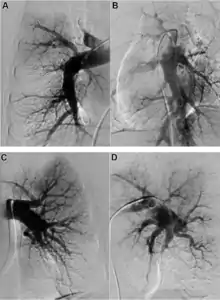

Early diagnosis still remains a challenge in CTEPH, with a median time of 14 months between symptom onset and diagnosis in expert centres.[7] A suspicion of PH is often raised by echocardiography, but an invasive right heart catheterisation is required to confirm it.[6] Once PH is diagnosed, the presence of thromboembolic disease requires imaging. The recommended diagnostic algorithm stresses the importance of initial investigation using an echocardiogram and V/Q scan and confirmation with right heart catheter and pulmonary angiography (PA).[8]

Both V/Q scanning and modern multidetector CT angiography (CTPA) may be accurate methods for the detection of CTEPH, with excellent diagnostic efficacy in expert hands (sensitivity, specificity, and accuracy of 100%, 93.7%, and 96.5% for V/Q and 96.1%, 95.2%, and 95.6% for CTPA).[9] CTPA alone cannot exclude the disease, but may help identify pulmonary artery distension resulting in left main coronary artery compression, pulmonary parenchymal lesions (e.g. as complications from previous pulmonary infarctions), and bleeding from bronchial collateral arteries.[10] Today, the gold standard imaging remains invasive pulmonary angiography (PAG) using native angiograms or a digital subtraction technique.